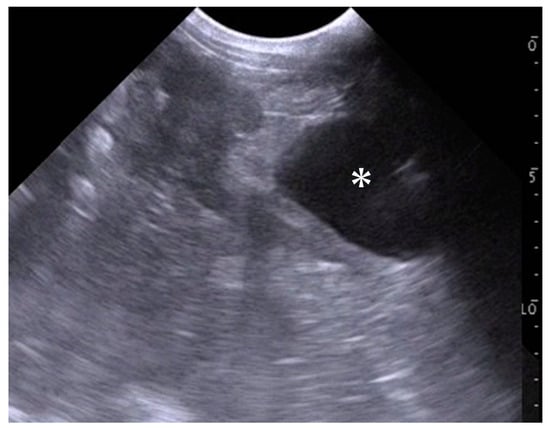

Ultrasonography: An ultrasound scanner (MyLabOne VET; Esaote Europe BV, Maastricht, Netherlands) was used to scan the animal in its standing position. The percutaneous application of a 2.5 MHz sector transducer to the caudal abdomen revealed an enlarged uterus within the lumen, which contained anechoic fluids (Figure 1).

In the present case, the combined use of ultrasonography, CT, and hysteroscopy was extremely helpful in diagnosing hydrometra and ovarian follicular cysts, guiding the decision to perform an ovariohysterectomy. In the diagnostic process using these modalities, the present case was initially examined using ultrasonography while scanning percutaneously via the abdominal wall. Transabdominal ultrasonographic scanning was chosen because the patient did not have a large enough body mass for the transrectal approach [7,18]. The transrectal scanning of small animals can lead to rectal damage [35]. Transabdominal scanning may be inferior to transrectal scanning in the visibility of the reproductive organs, possibly because of the differences in the ultrasound frequency of the applicable transducer, as previously ranging between 3.0 and 6.5 MHz [2,5,11,19,21,22,23] and between 5.0 and 10.0 MHz [6,7,8,11,13,18,20,21], respectively. Additionally, it is challenging to demonstrate the whole structures of the reproductive organs using transabdominal scanning. This may have limited the diagnostic information obtained by ultrasonography in the present case. Transvaginal ultrasonography could have been utilized as the alternative scanning method to demonstrate the pathological reproductive tract because it has previously helped the identification of early pregnant uteruses in goats [36].

The previous applications of ultrasonography for sick or infertile female goats could help identify the varying prevalence of hydrometra, accounting for 1.4 to 51.0% [5,6,7,8,21]. The ultrasonographic observations of this disease are characterized by varying amounts of anechoic fluids within the uterine lumen, where small hyperechoic deposits float occasionally [5,7,10,11,21,35]. The echogenicity of the intrauterine effusion was higher on the ultrasonogram of pyometra than that of hydrometra and endometritis [10,11,22]. However, differentiating hydrometra from pyometra may occasionally be difficult [35] because of the varying echogenicity of intrauterine effusion, which appears anechoic [6,7] to hypoechoic [8]. Additionally, the ultrasonographic findings of hydrometra showing small amounts of intrauterine effusion can be misdiagnosed as early pregnancy when the echotextures of the fetus and placentome cannot be found [7,35]. In terms of the ultrasonographic appearances of uterine tumors compared with those of hydrometra, these uterine diseases can be differentiated based on the ultrasonographic findings observed in half of the previous caprine cases, including the formation of hyperechoic mass structures derived from the endometrium and muscular layers and multifocal, anechoic, cystic lesions diffused within uterine walls [12,13,19]. However, intrauterine fluid retention was the common ultrasonographic finding among these uterine diseases, as reported in 38% of examined caprine cases with uterine tumors [12,13,19]. Thus, using ultrasonography alone makes it difficult to distinguish common uterine diseases [10].

Figure 1. Ultrasonographic appearance of the uterus when scanning percutaneously. Anechoic fluid (asterisk) is seen within the enlarged uterine lumen. Scale = 10 mm.